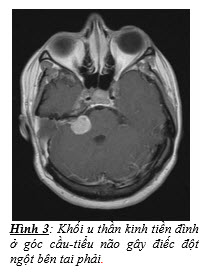

- Các bệnh lý tân sinh u: u góc cầu-tiểu não, u ống tai trong, u di căn từ nơi khác đến xương thái dương hay màng não.

Trong số các nguyên nhân ĐĐN, khoảng 0,8 - 4% các người bệnh có u ống tai trong hoặc u góc cầu¬-tiểu não (Hình 3), ngay cả khi người bệnh đã hồi phục thính lực hoàn toàn cũng không thể hoàn toàn loại trừ các nguyên nhân này. Do đó, chụp cộng hưởng từ (MRI) có tiêm gadolinium là xét nghiệm phù hợp nhất để loại trừ các bệnh lý sau ốc tai. Nếu không thể chụp cộng hưởng từ, người bệnh nên được đo điện thính giác thân não hoặc đo lại thính lực đồ trong quá trình điều trị, các bất thường kéo dài trên 2 xét nghiệm này có thể gợi ý cho các bệnh lý sau ốc tai.